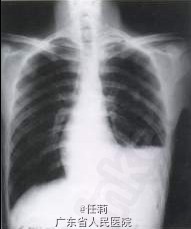

T 36.5℃,左下肺叩诊浊音,听诊呼吸音低,双肺未闻及干、湿性罗音。心、腹检查未见明显异常。脊柱、四肢无畸形,各关节活动如常,无红肿或压痛。 辅查:胸腔积液检查:淡粉色乳糜样,有核细胞总数900/mm3,白细胞50/mm3,比重1.038,蛋白10.2g/dl,乳酸脱氢酶64U/L,胆固醇80mg/dl,甘油三酯235mg/dl,乳糜试验(+),普通细菌培养(—),镜下见大量淋巴细胞、间皮细胞,未见瘤细胞。 胸部高分辨CT:双肺纹增多,紊乱,双肺弥漫性薄壁囊泡样改变。X线胸片左侧胸腔积液。

诊断为:淋巴管平滑肌瘤病 患者入院后予胸腔穿刺抽液及对症治疗,经专科讨论考虑为肺淋巴管肌瘤病的可能性大,考虑在手术结扎胸导管的同时行肺活检以进一步确诊。患者接受全麻下开胸手术,结扎胸导管,滑石粉胸膜表面涂抹以达到胸膜粘连的目的,并行肺活检。术中见双肺弥漫性小泡状改变,组织水肿,经病理检查确诊为淋巴管平滑肌瘤病。